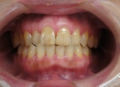

前歯部インプラント骨移植同時症例

大学病院よりご依頼いただいた症例。仮歯が入っていますが、欠損部歯茎が大きくへこんでいて、CT画像ではパノラマレントゲンで想定していたよりもかなり大きく骨がなかったですが、インプラント手術と骨の移植を同時に行い審美的にも回復しました。また同時に行うことにより治療期間が9か月→4か月の短縮されました。被せ物には審美性を考慮して土台からセラミックを使用しました。